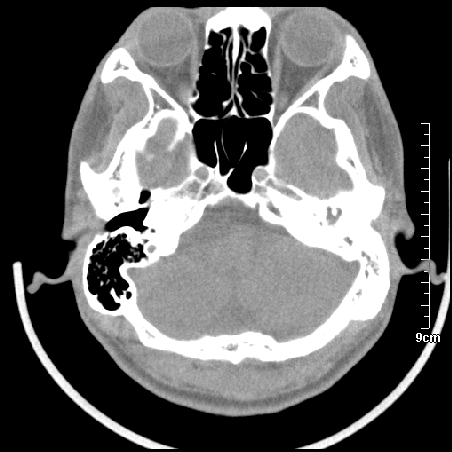

病例1

m/46y 头晕.耳鸣半月余 有乳突炎病史

左侧板障型乳突。

左侧慢性中耳炎伴胆脂瘤形成。